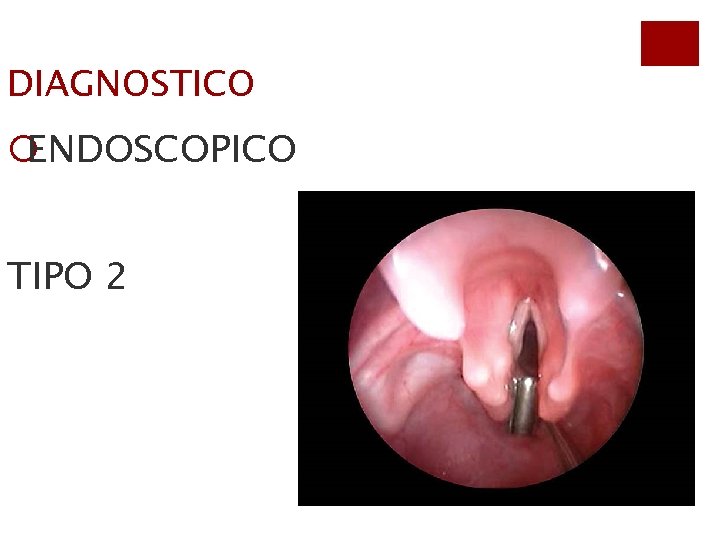

DIAGNOSTICO ¡ENDOSCOPICO TIPO 2